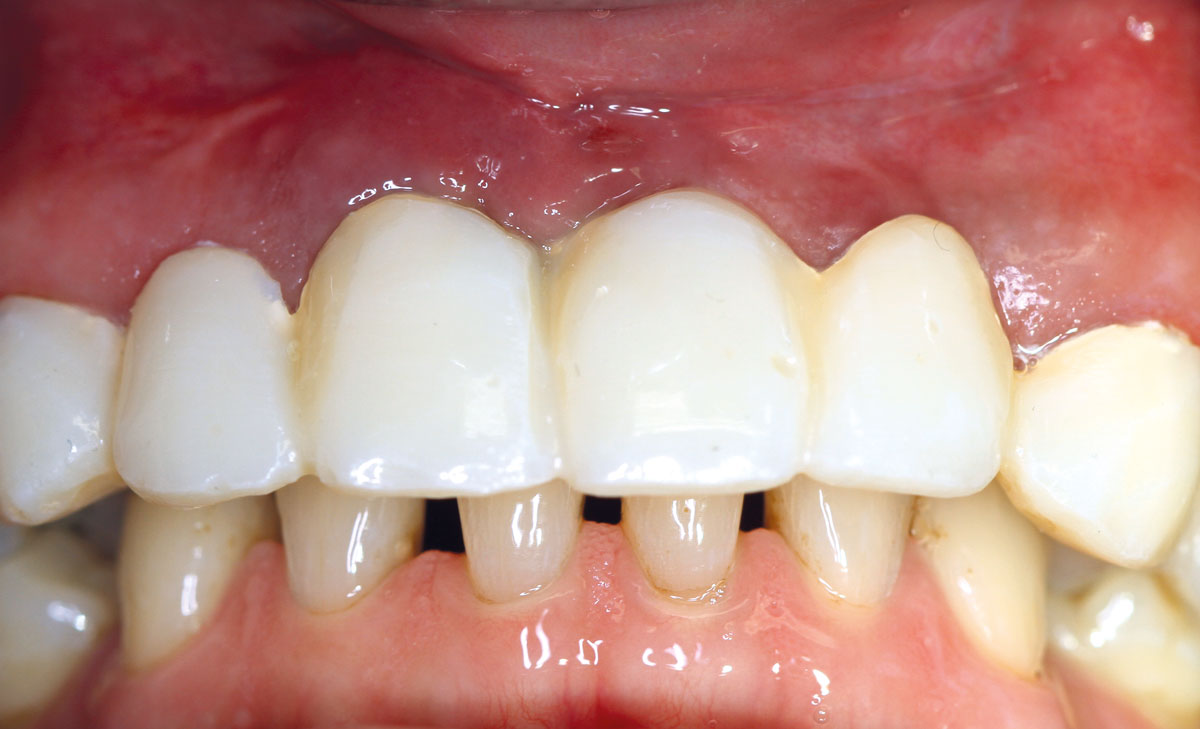

1/17 - Pre-operative clinical situation: changed color in the gingiva in the front maxillaRestoration of all four incisors with maxgraft® bonebuilder - Dr. Dr. Dr. O. Blume

Pre-operative clinical situation: changed color in the gingiva in the front maxilla